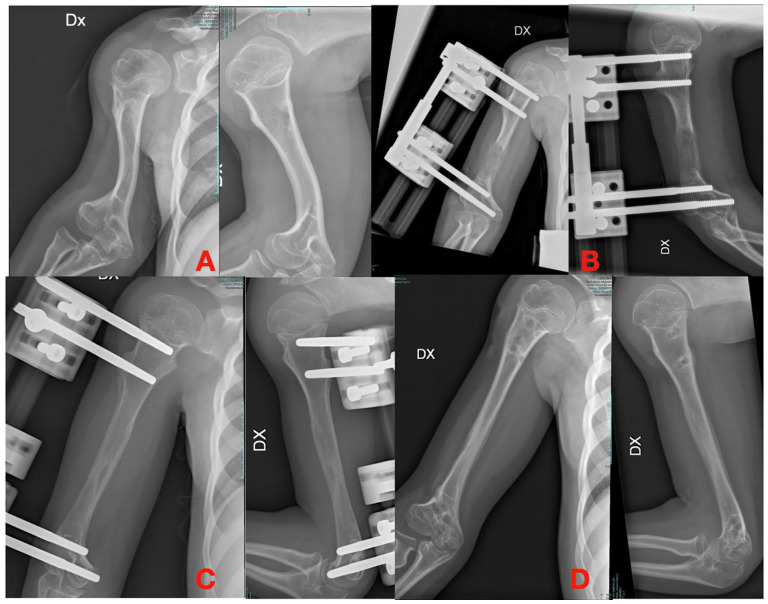

使用外固定架是骨科医生治疗许多临床疾病的文化背景的一部分。多年来,固定架的设计和生物力学知识导致了不同的解决方案和技术,骨延长及其更好的理解与外固定架的发展和牵张成骨生物学原理的应用一起出现。作者对儿童上肢使用外固定架和延长系统进行了文献综述。尽管外固定架在上肢的应用比下肢的应用要有限得多,但有外伤、先天性、肿瘤和感染性病因的迹象。然而,尽管钢板、螺钉和髓内延长钉的新系统得到了广泛应用,但何时使用外固定的问题仍未得到解决。另一个争论点是使用单侧或圆形框架肱骨延长和纠正前臂畸形的多发性遗传性外骨骼疾病(MHE)或桡骨纵向缺陷后遗症。单轴固定架在所有检查区域的骨骼延长中都保持着突出的作用,尽管其作用可能被机动髓内钉所超越,特别是在肱骨延长方面。六足系统可能代表了未来多平面前臂畸形的矫正;然而,为了更好地验证其应用和优势,需要在更大的系列上进行多中心研究。

The use of external fixators is part of the cultural background of orthopedic surgeons in treating numerous clinical conditions. Over the years, fixator design and biomechanical knowledge have led to different solutions and techniques, and bone lengthening and its better understanding come together with the development of external fixators and the application of the biological principle of distraction osteogenesis. The authors conducted a literature review about using external fixators and lengthening systems in pediatric upper limbs. Despite the applications of external fixators in upper limbs remaining much more limited than those of the lower limbs, there are indications of traumatic, congenital, tumor, and infectious etiologies. However, despite the spread of new systems of plate and screws and intramedullary lengthening nails, the problems about when to use external fixation remain unsolved. Another debated point is about using monolateral or circular frames for humeral lengthening and the correction of forearm deformities in multiple hereditary exostoses disease (MHE) or radial longitudinal deficiency sequelae. Monoaxial fixators retain a prominent role for skeletal lengthening in all the districts examined, although their role could be outclassed by the motorized intramedullary nails, especially for humeral lengthening. Hexapod systems are likely to represent the future for the correction of multiplanar forearm deformities; however, multicenter studies on larger series will be necessary to better validate their applications and advantages.